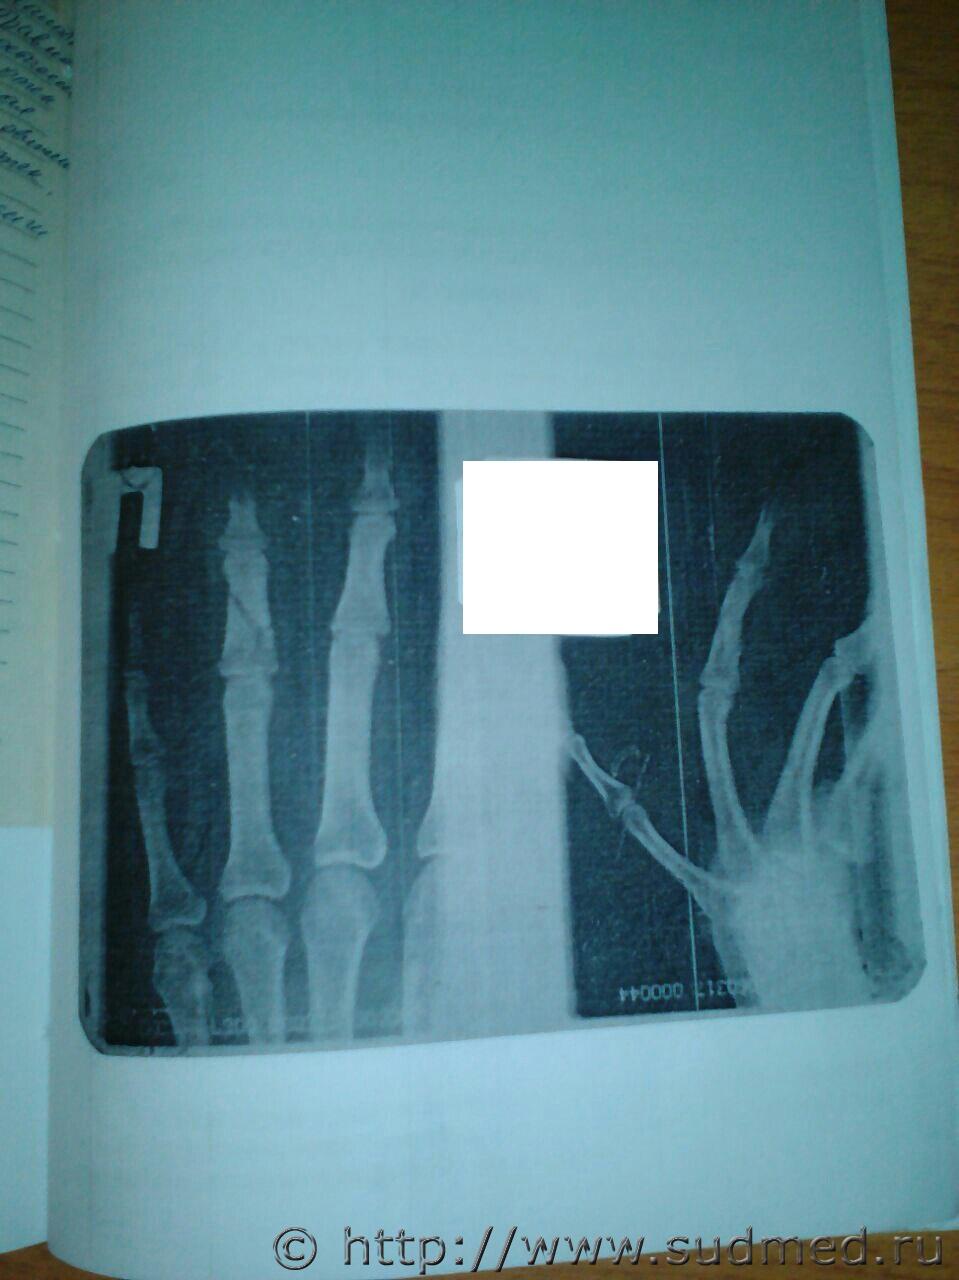

Здравствуйте, помогите, пожалуйста, разобраться и понять перспективы и выстроить грамотно линию защиты. Невиновного человека хотят привлечь по ст. 112 ч. 1 УК РФ. Экспертиза проведена с процессуальными нарушениями. Нам не предоставили возможность задать свои вопросы. Эксперт написал в заключении на поставленный вопрос о переломе пальца со слов потерпевшего - не исключено. Потерпевший утверждает, что палец был сломан при попытке вырвать телефон. Дословно из показаний на очной ставке: "Он меня схватил своей рукой за запястье правой руки, потянул на себя, а второй рукой начал вынимать из ладони телефон, покручивая мои пальцы в разные стороны, я закричала от резкой боли..." Из показаний известно (со слов пострадавшей), что перелом со смещением. Кроме снимка, к сожалению, пока никакой информацией не обладаем. Интересует объективное независимое мнение (заключение):

1.С учетом особенностей линии излома к какому виду относится данный перелом (каков характер повреждений)?

2. Возможные механизмы (способы) получения травмы.

3. Мог ли данный перелом возникнуть в результате удара о тупой предмет? Могло ли данное повреждение (перелом) возникнуть вследствие удара (тупым) предметом?

4. Возможен ли такой перелом при защемлении пальца между двумя твердыми предметами; при движении холодильника (рука на угловой части холодильника), или между холодильником и дверной коробкой, путем одновременного скручивания, сдавливания, попадания на углы дверной коробки и (или) угол холодильника? Между двумя твердыми неравномерными поверхностями?

5. Не характерно ли перелому пальца при скручивании: перелом в сочетании с повреждением связок, сухожилий, переломо-вывих?

1.оскольчатый внутрисуставной перелом проксимального эпифиза, верхней и средней третей диафиза средней фаланги четвертого пальца правой кисти с допустимым (незначительным) угловым и ротационным смещением отломков.

2-5. Образование такого перелома нехарактерно для насильственного разгибания или кручения пальца.

Наиболее типично формирование такого перелома от действия повреждающей силы по оси кости, что могло быть при сильном и резком ударе выпрямленным пальцем или при ударе по кончику выпрямленного пальца вдоль его оси.

Маловероятно, но не исклюдчается полностью, получение этого перелома от удара по его области.